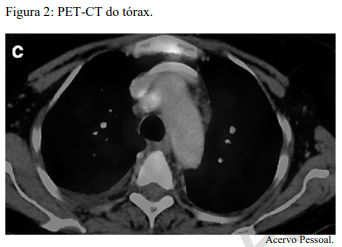

Um paciente de 62 anos de idade, tabagista ativo, cerca de 180 anos-maço, queixa-se de cansaço, tosse seca e perda de peso; por isso, procurou atendimento médico. O paciente referiu que pesava 100 kg e perdeu 10 kg. Realizou-se tomografia computadorizada de tórax, com evidência de lesão sólida de 2,1 cm em topografia de lobo inferior à direita, sólida, espiculada, com margens bem definidas e densidade de partes moles, assim como linfonodomegalia paratraqueal direita de 1,5 cm, paratraqueal esquerda de 1,2 cm e subcarinal de 2 cm. O paciente foi submetido a PET-CT de corpo inteiro, com evidência de hipercaptação de radiofármaco pela lesão (SUV 12) e eplo linfonodo representado na figura 2 a seguir.

O linfonodo hipercaptante no PET desse paciente, representado na figura 2, trata-se do paratraqueal direito.